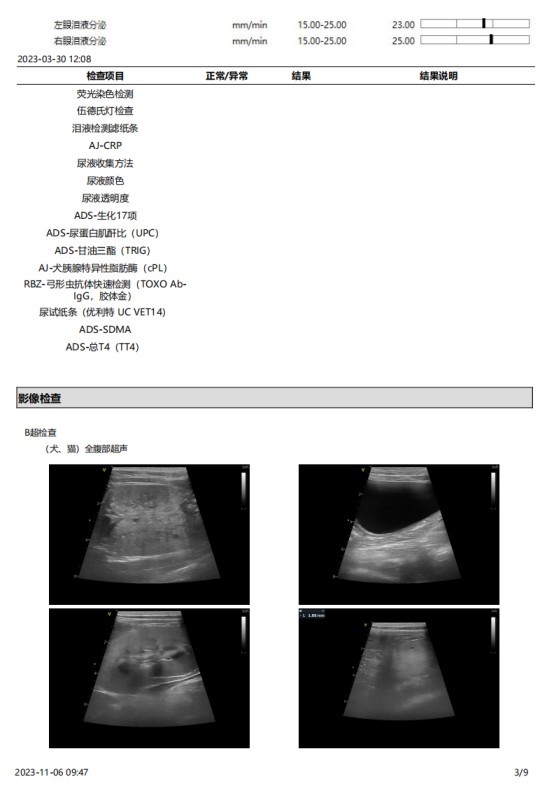

2023 年 3 月份检查结果